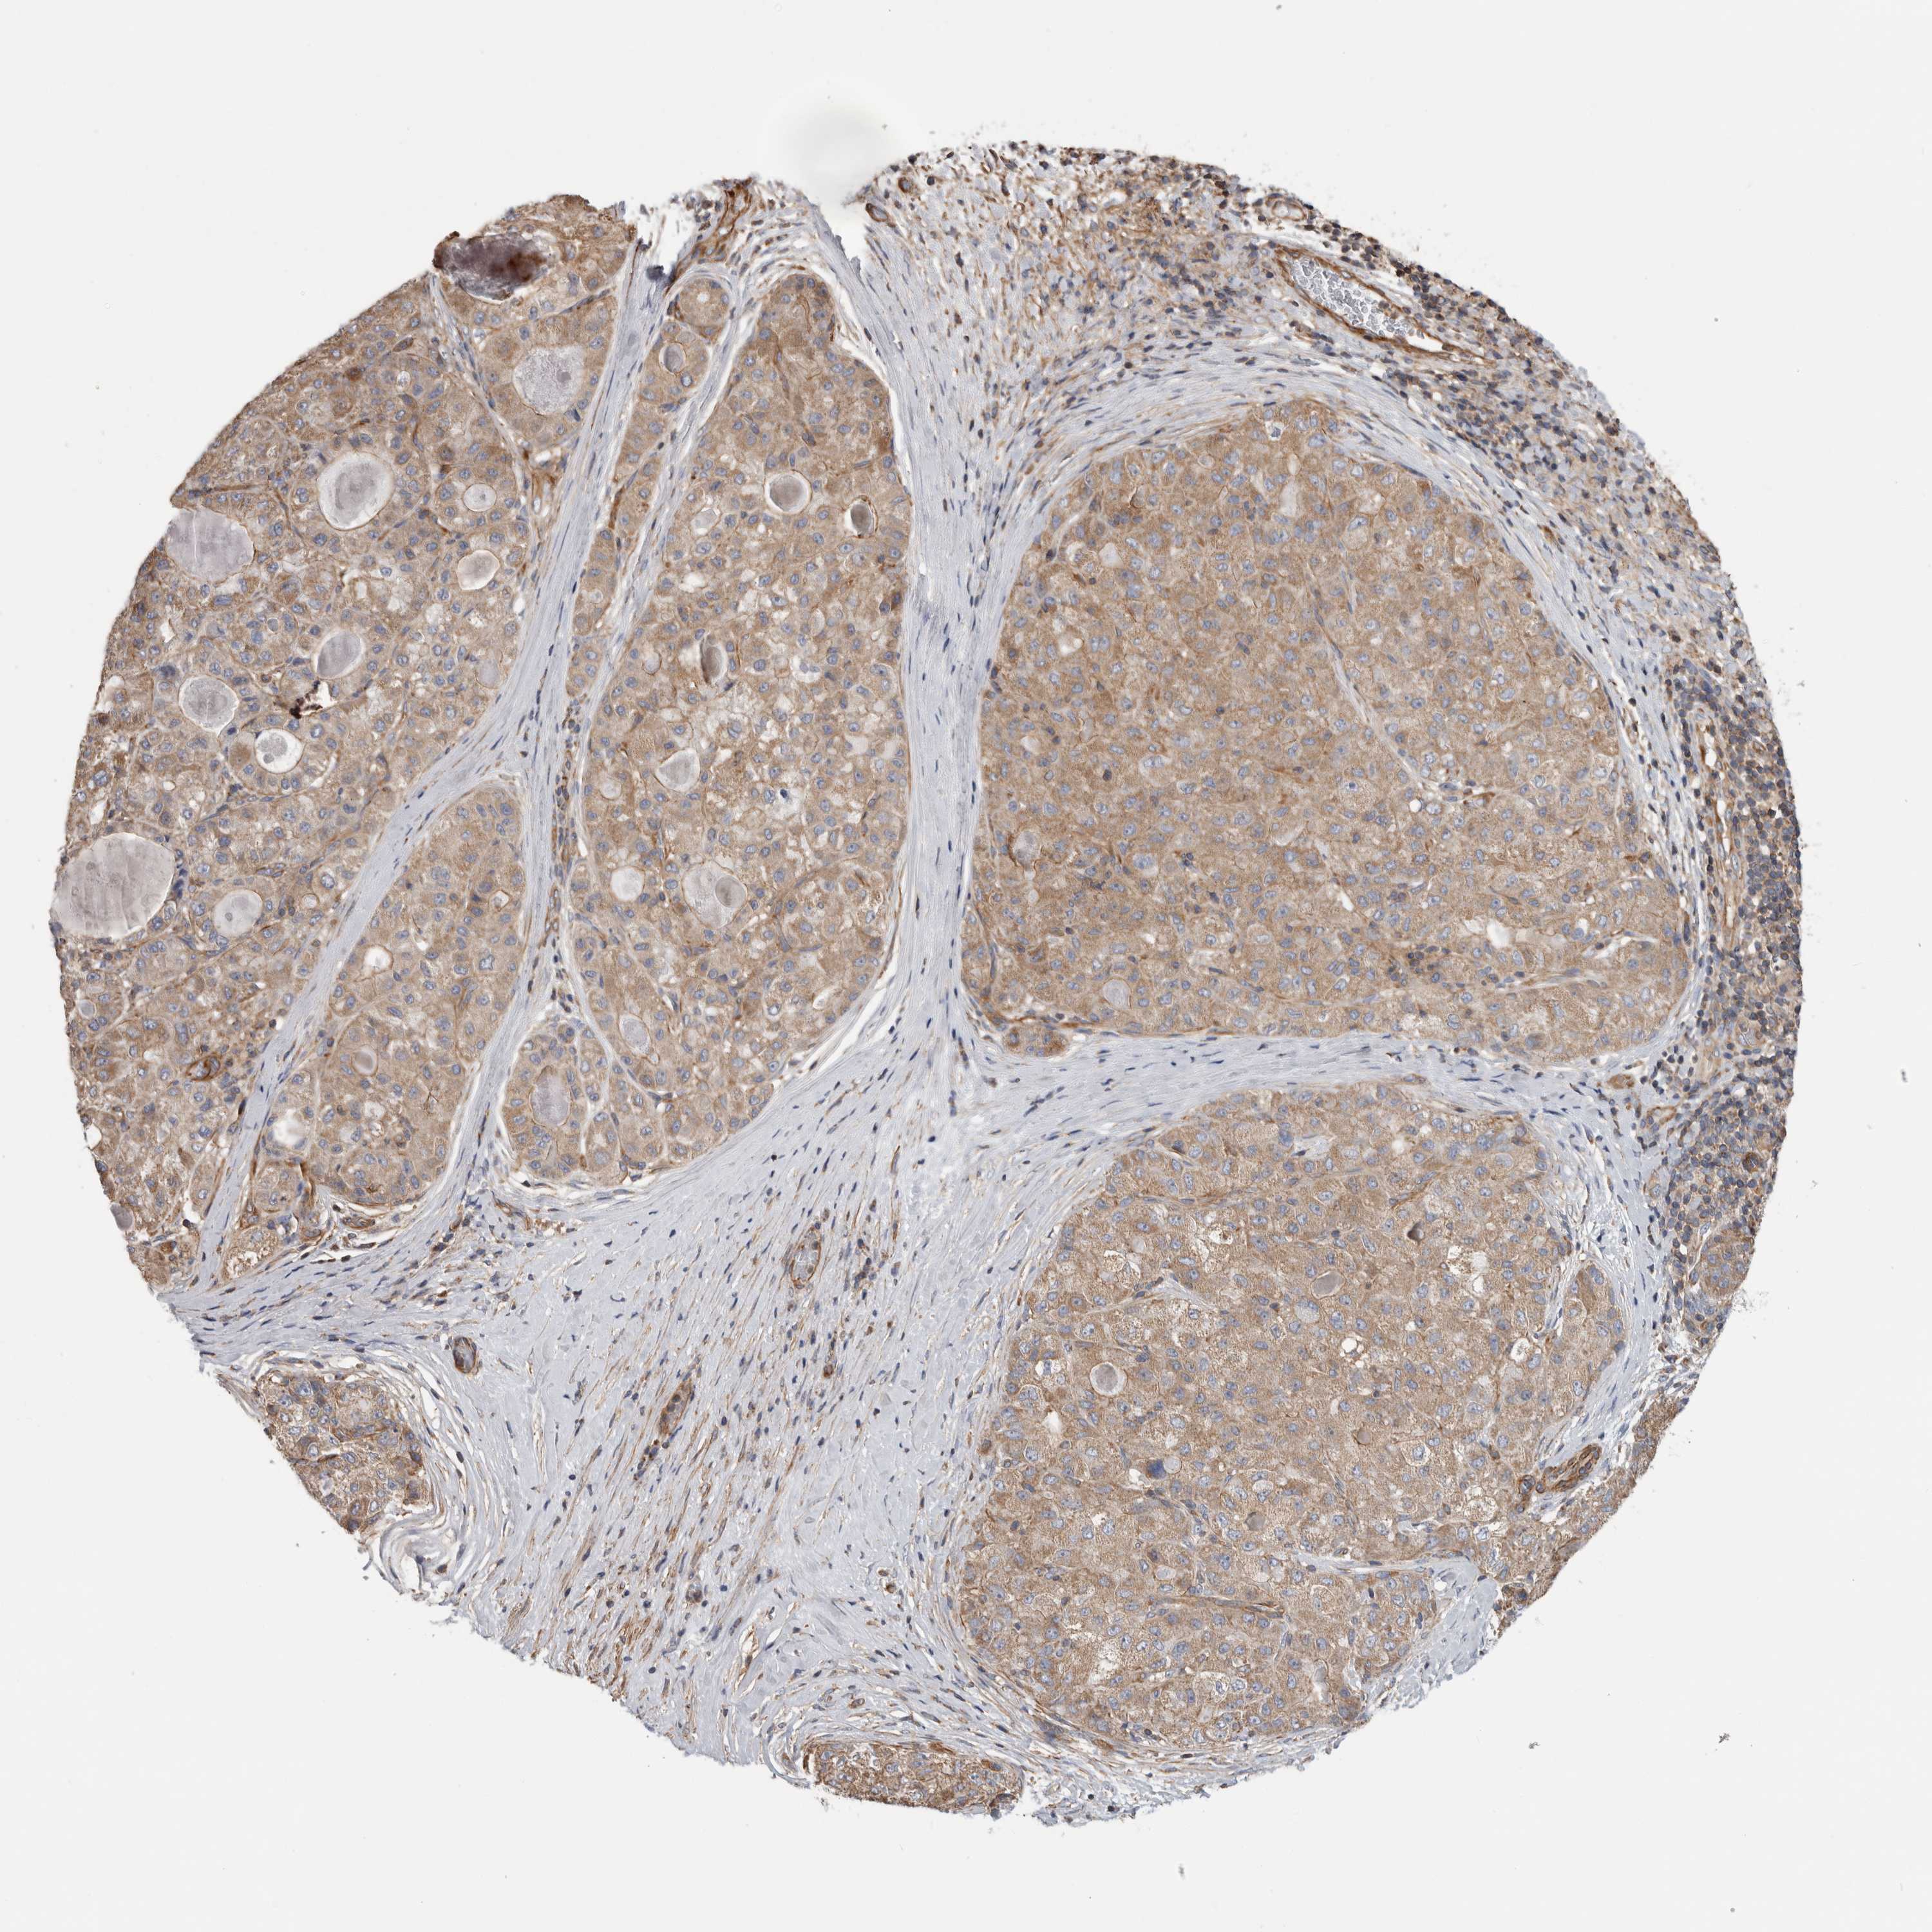

LIVER CANCER - Protein expressioni

A mouse-over function shows sample information and annotation data. Click on an image to view it in a full screen mode. Samples can be filtered based on level of antibody staining by selecting one or several of the following categories: high, medium, low and not detected. The assay and annotation is described here.

Note that samples used for immunohistochemistry by the Human Protein Atlas do not correspond to samples in the TCGA dataset.

Antibody stainingi

Antibody staining in the annotated cell types in the current human tissue is reported as not detected, low, medium, or high, based on conventional immunohistochemistry profiling in selected tissues. This score is based on the combination of the staining intensity and fraction of stained cells.

Each image is clickable and will lead to virtual microscopy that enables deeper exploration of all samples and also displays staining intensity scores, fraction scores and subcellular localization as well as patient and tissue information for each sample.

Antibody HPA018150

Antibody HPA026834

Staining

High

Medium

Low

Not detected

Intensity

Strong

Moderate

Weak

Negative

Quantity

>75%

75%-25%

<25%

None

Location

Nuclear

Cytoplasmic/membranous

Cytoplasmic/membranous,nuclear

Cholangiocarcinoma

Carcinoma, Hepatocellular, NOS